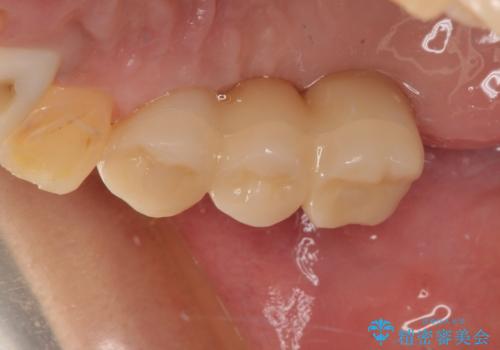

臼歯はもはや咬み合わせに寄与していない状態であり、3歯を抜去してインプラント2本埋入によるブリッジ補綴を計画しました。

臼歯部は前歯以上に炎症が酷く、抜歯即時埋入不可と判断されましたが、従来法よりは短期間で終えることができました。